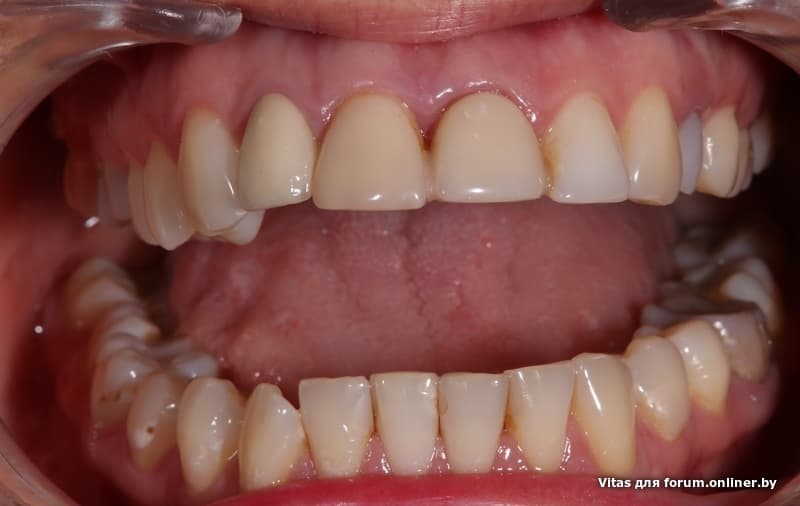

Угадаете где имплант?